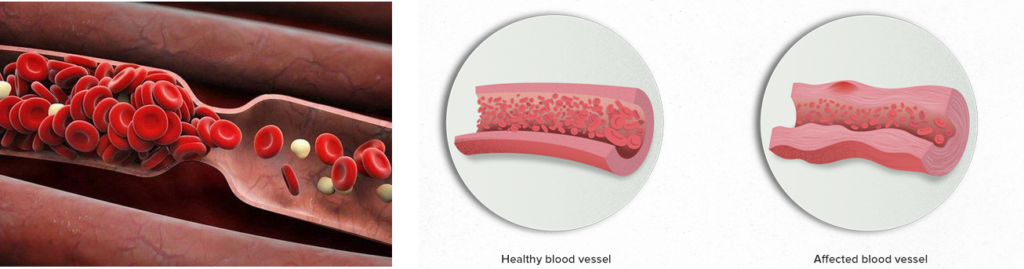

Πρόκειται για μια ομάδα νοσημάτων που προκαλούν φλεγμονή στα αιμοφόρα αγγεία.

Μπορεί να βλάψουν τα αιμοφόρα αγγεία προκαλώντας στενώσεις, αποφράξεις ή και ανευρύσματα και να τα εμποδίσουν να μεταφέρουν αίμα σε μέρη του σώματος που το χρειάζονται. Η αγγειίτιδα μπορεί να επηρεάσει πολλά διαφορετικά μέρη του σώματος.